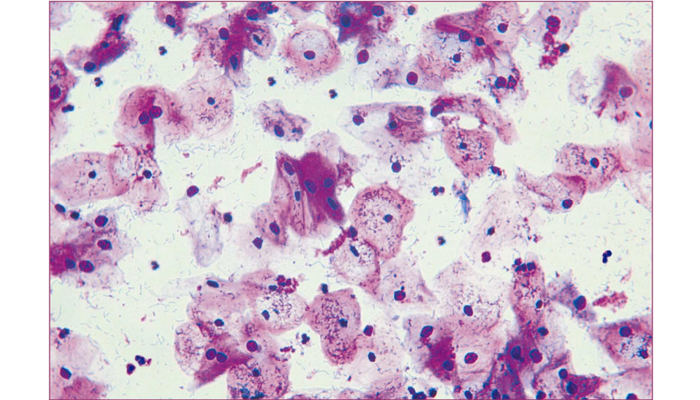

The samples of exfoliative cell have extensive sources, which include cervical smears, endometrial smears, sputum smears, bronchial washing and swab smears, mouth and esophagus smears, gastric juice smears, urine smears, celiac and thorax effusion smears. Traditionally, the standard methods of exfoliative cell stain in clinic are Papanicolaou stain and Hematoxylin-Eosin stain. Theimproved Baso Exfoliative Cell Stain is rapid-to-use and provides clearer results.For disease diagnosis, the BASO staining result is an important reference indicator , as good as Papanicolaou stain.

This kit is an improvement of the Romanowsky Stain technique. It includes acid stain (Eosin) and alkaline stain (Methylene blue). For different cells, the affinity to the acid and alkaline stains varies. Thus, different cells will exhibit different colors after staining, rendering its shape and characteristics identifiable.